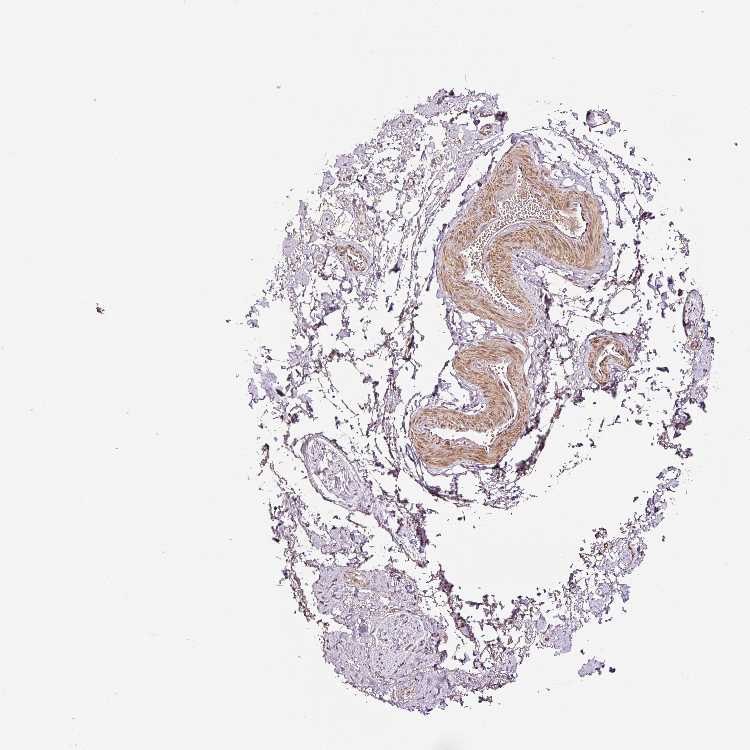

ADIPOSE TISSUE - Antibody stainingi

Antibody staining in the annotated cell types in the current human tissue is reported as not detected, low, medium, or high, based on conventional immunohistochemistry profiling in selected tissues. This score is based on the combination of the staining intensity and fraction of stained cells.

Each image is clickable and will lead to virtual microscopy that enables deeper exploration of all samples and also displays staining intensity scores, fraction scores and subcellular localization as well as patient and tissue information for each sample.

Antibody HPA049123Antibody HPA058507Antibody CAB004557

Adipocytes LowNot detectedMedium